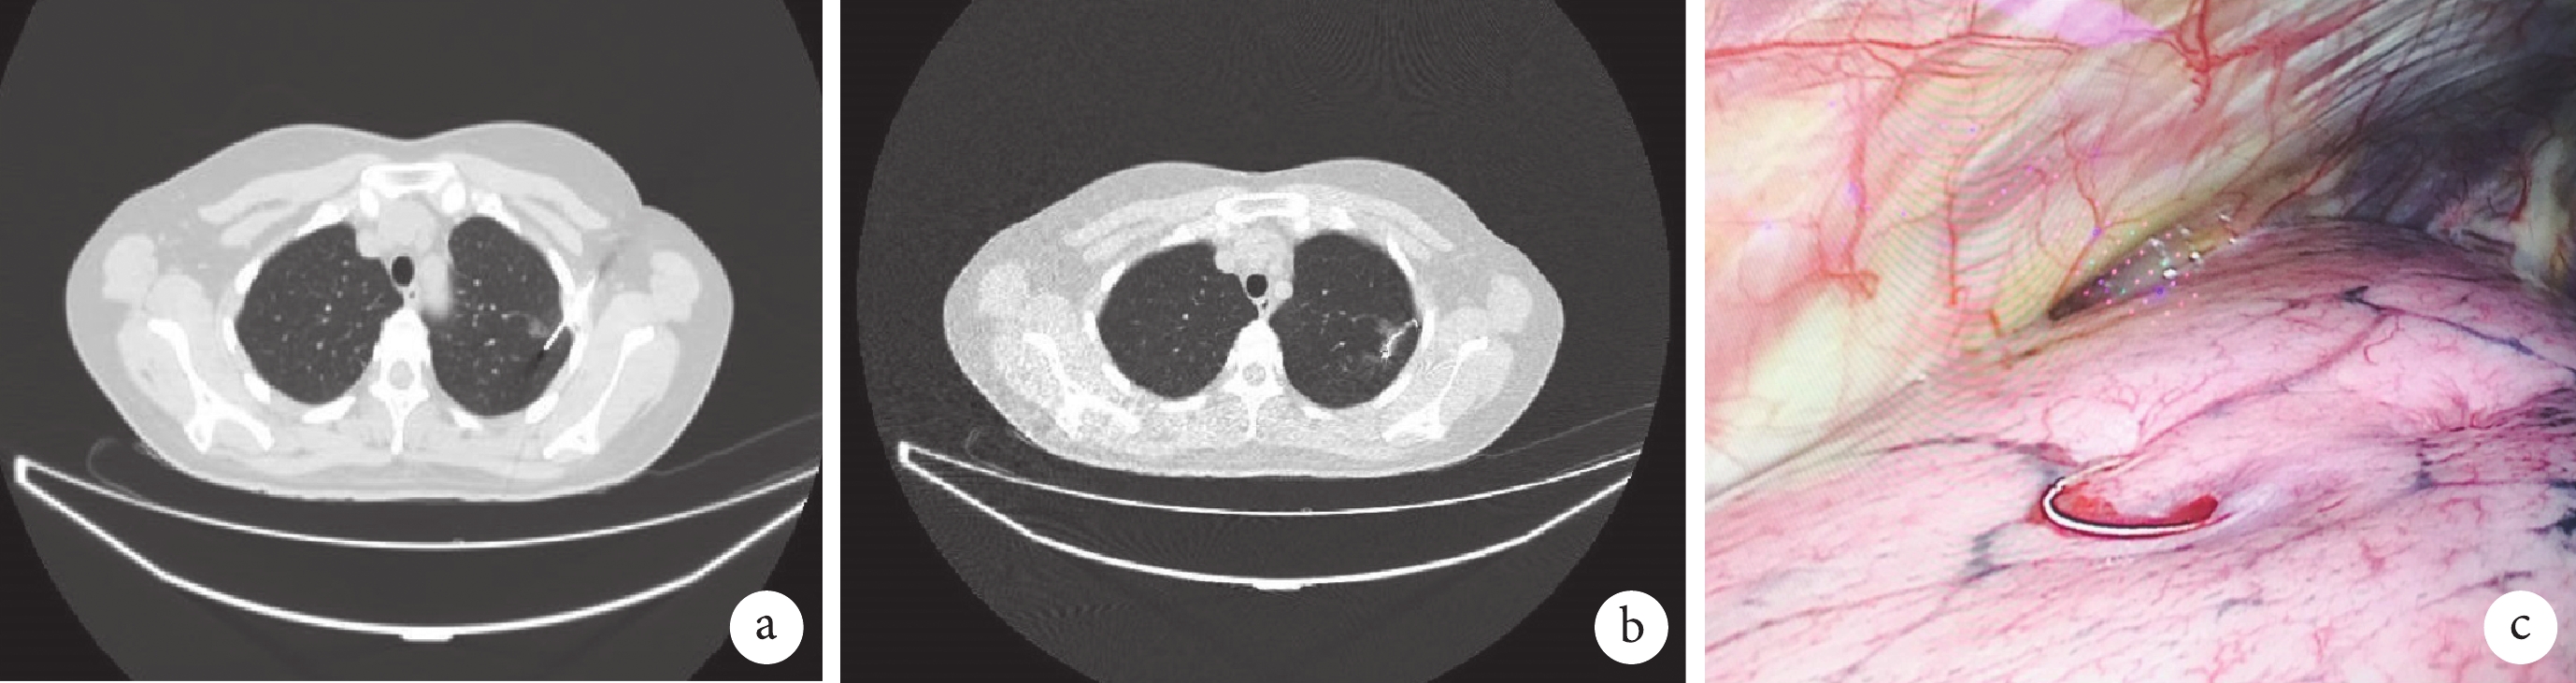

a:CT 引導下穿刺至結節附近;b:結節旁釋放彈簧圈,保留尾絲于胸膜外;c:術中可見肺表面彈簧圈尾絲

微彈簧圈組:(1)根據影像學資料及手術方案,設計體位及進針入路;(2)擺好體位后重新掃描 CT,確定進針入路及進針深度;(3)常規消毒、鋪巾,2% 利多卡因局部麻醉,穿刺進針至預期深度;(4)再次掃描 CT 明確進針位置及深度,滿意后,經穿刺針釋放部分彈簧圈;如位置不滿意,根據 CT 掃描結果調整滿意后再釋放彈簧圈;(5)將穿刺針退至胸膜腔層面,釋放剩余彈簧圈,讓部分彈簧圈位于胸膜表面;(6)定位完成后再次掃描 CT 評估患者氣胸及肺內出血情況,掃描可見彈簧圈大部分位于肺內視為定位成功;見圖 4。方法及穿刺圖可見我單位既往報道[3]。